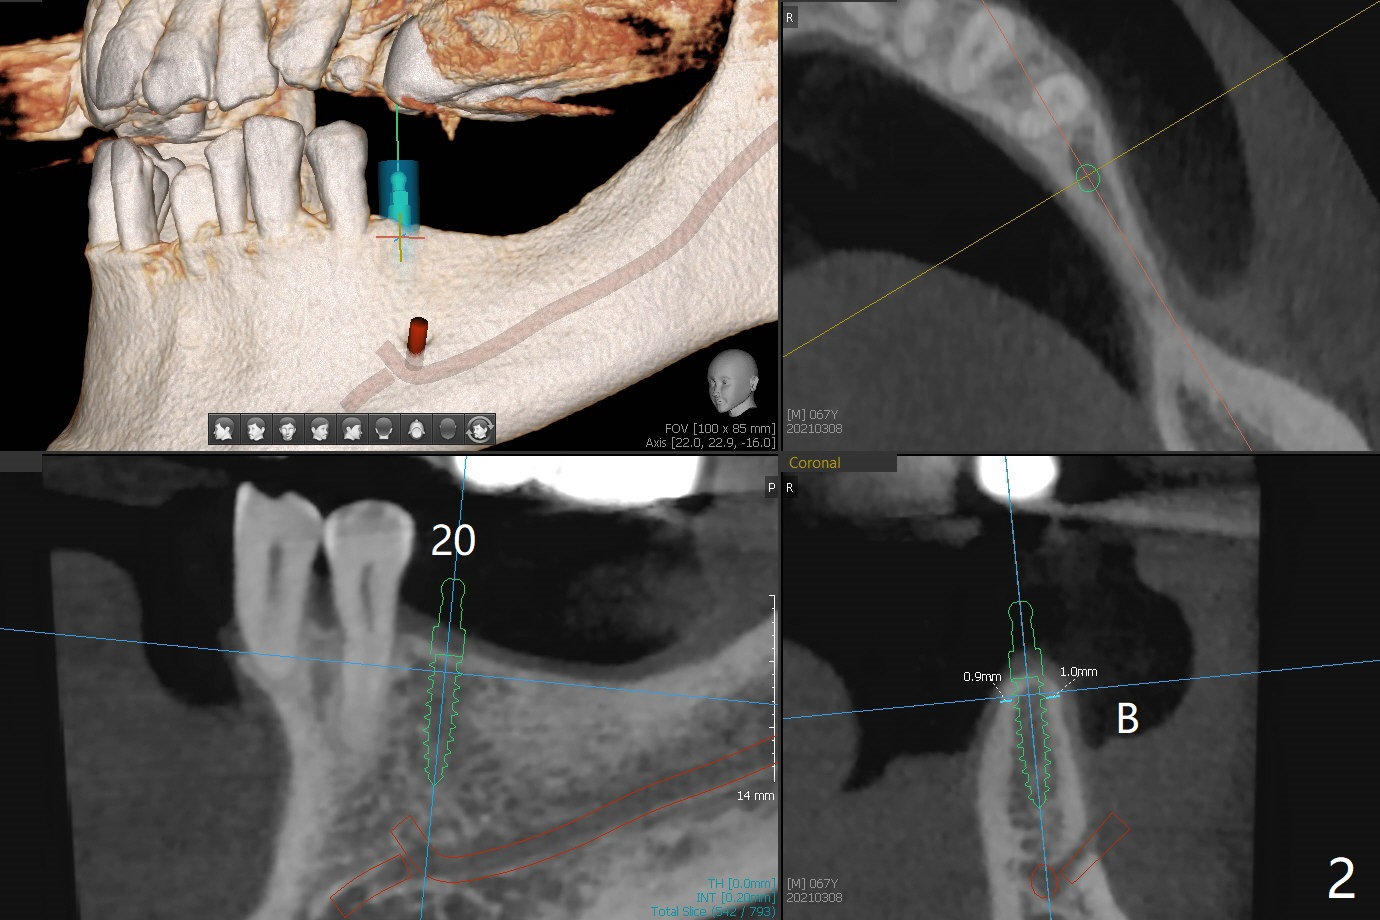

A 67-year-old man requests lower implants (19,20,25) to replace lower RPD with history of food impaction under the partial 5 months post cementation of the upper implants (Fig.1). Due to the atrophic mandible, 1-piece implants will be placed with guide (Fig.2-5) and free hand (Fig.6). Incision will be made at all of the sites for vision and bone graft.